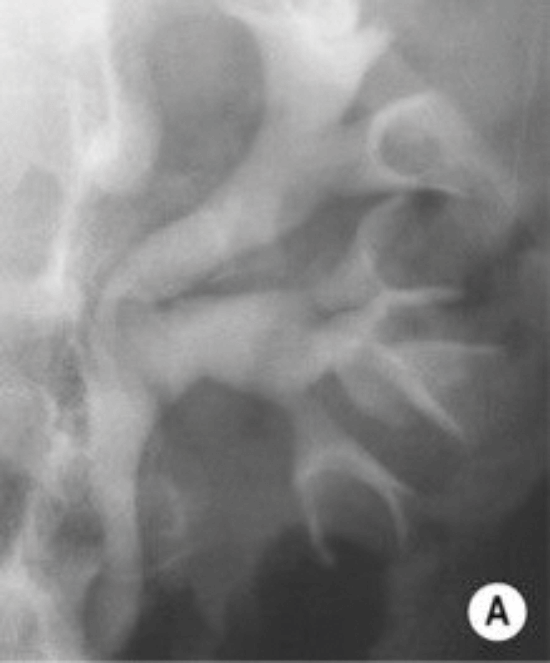

Figure 2a.

- Figure 2 shows other radiological features of one of these possible causes. What is the likely diagnosis? How often does this condition affect the urinary tract?

- What pathology can it cause in the urinary tract?

- What are the ‘classical features’ seen on an intravenous urogram (IVU)?

-

TB, 15% genitourinary tract involvement. A: left autonephrectomy, B: non-functioning right kidney with left sided infundibular scarring and caliectasis, left distal ureteric stricture, small capacity bladder.

Kidney (haematogenous spread): infundibular stenosis and calyceal dilatation, papillary necrosis, ‘putty’ kidney, autonephrectomy. Ureter: lower ureteric strictures, gold hole ureteric orifice. Bladder: ‘thimble’ bladder, calcification, reduces capacity. Rarer: prostatitis, urethritis, epidydmitis (string of beads), orchitis.

Renal calcification, infundibular stenosis, autonephrectomy, ureteric calcification / strictures, calcified bladder, small volume bladder.